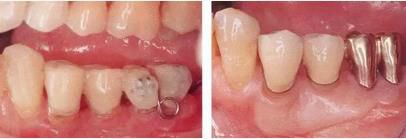

360截圖20170422101744009.jpg

▲圖5-1,2

▲圖5-1 左下5舌側(cè)移位,頰系帶高位附著,附著齦不足,口腔前庭狹小,左下6根分叉病變,左下7擴散性骨組織吸收深達根尖部等,存在非常多的問題。

▲圖5-2 確認(rèn)左下7骨組織吸收深達根尖部,初期治療時拔除。將左下7拔除后的X光片。

360截圖20170422101820545.jpg

▲圖5-3,4

▲圖5-3 開始正畸治療時的側(cè)方照。預(yù)計使左下6向遠(yuǎn)中、左下5向頰側(cè)方向移動。

▲圖5-4 在左下4~右下3的舌側(cè)種植支抗,并用金屬網(wǎng)增加強度。